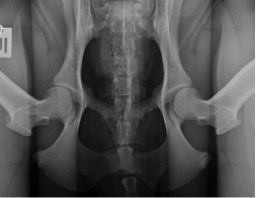

Bei der FCI-Methode werden Hunde je nach Rasse im Alter von zwölf bis 24 Monaten untersucht. Dabei werden die Patienten in Narkose mit gestreckten Gliedmaßen geröntgt, so dass die Oberschenkelknochen parallel zueinander liegen. Diese relativ unnatürliche Haltung ist die Grundlage zur Beurteilung des Grades der HD auf den Röntgenaufnahmen. Der Tierarzt beurteilt das Aussehen von Oberschenkelkopf und Hüftpfanne und deren Passform zueinander. Darüber hinaus misst er den sogenannten Norberg-Winkel, der bei einem HD-freien Hund 105 Grad und mehr beträgt. Auf diese Weise lassen sich fünf Schweregrade von A (HD-frei) bis E (schwere HD) der Hüftgelenksdysplasie unterscheiden.

Für das PennHIP® Verfahren werden drei Röntgenaufnahmen angefertigt:

Bei der Distraktionsaufnahme wird ein sogenannter Distraktor zwischen die Beine des Tieres gelegt. Wenn der Untersucher die Beine des Hundes gegen den Distraktor drückt, wird der Oberschenkelkopf aus der Hüftpfanne „herausgezogen“. Je weiter das möglich ist, desto lockerer ist die Hüfte und desto größer die Wahrscheinlichkeit, dass ein Hund an einer HD leiden wird. Das Maß für die Lockerheit des Hüftgelenks ist dabei der Distraktionsindex (DI).